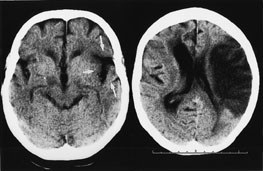

De følgende eksempler er hentet fra pasienter innlagt i Nevrologisk avdeling, Haukeland Sykehus, med akutt cerebral iskemi og undersøkt med CT innen tre timer og ti minutter etter symptomdebut (bildet til venstre, fig 1 – 4) og med oppfølgende CT (bildet til høyre, fig 1 – 4). Bildene illustrerer de forannevnte kardinaltegn (tab 1).

Hypodensitet i basalgangliene (fig 2). Ved et mediainfarkt er basalgangliene (nucleus caudatus, putamen og pallidum) ofte først rammet. Putamen er fysiologisk mer hyperdens enn pallidum.

Hypodensitet i insula (fig 3). Iskemi fører til vanskeligheter med å diskriminere cortex fra subkortikalt vev i insula og fører til tap av ”insula ribbon” (cortexgrensen).